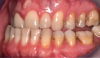

Fig 18. Bite interdigitation to finalize surgical orthodontic correction. After orthodontics, periodontal plastic surgery, bleaching, microabrasion, and restorative dentistry were performed.

Fig 19. Bite interdigitation to finalize surgical orthodontic correction. After orthodontics, periodontal plastic surgery, bleaching, microabrasion, and restorative dentistry were performed.

Fig 20. Bite interdigitation to finalize surgical orthodontic correction. After orthodontics, periodontal plastic surgery, bleaching, microabrasion, and restorative dentistry were performed.